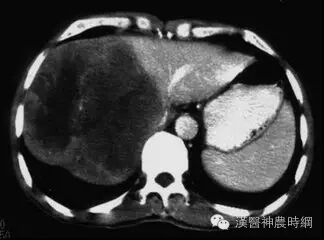

2.计算机X线体层扫描(CT)  CT是一种安全、无创伤、高分辨力的检查方法。对肝癌的定位诊断很有价值。CT能显示肿瘤的大小、位置、数目及与周围脏器和大血管的关系,可检出1cm左右的早期肝癌。并有助于了解是否伴发肝外转移,如肝门淋巴结,胰头后淋巴结等。结合增强扫描可以判断病变的性质,对肝癌与肝血管瘤的鉴别有较大的价值。平扫下肝癌多为低密度占位,边缘清晰或模糊,部分有包膜的肝癌可显示晕圈征。较大的肝癌可见更低密度的坏死区,少数肝癌可见钙化。增强扫描有滴注法、大剂量推注、推注加动态扫描等。肝癌在动脉期尤以注药20s内强化最为明显,癌灶密度高于周围肝组织。30~40s后造影剂进入细胞间隙转入实质期,病灶又恢复为低密度,显示更为清晰。近将肝动脉造影与CT检查相结合,开展CT动脉造影(CTA)和CT动脉门脉造影(CTAP),对提高小肝癌的检出率有一定价值。也有人在CT检查前一周经肝动脉插管注入碘化油(lipiodo1),再做CT扫描,这种lipiodol-CT可检出0.5cm的小肝癌。对于<1cm的肝癌,Uchida报告US、CT、肝动脉造影和几种CT检查的分辨力为:US 63%、普通CT 12%、滴注法增强扫描65%、CTA 71%、CTAP 80%、lipiodol-CT 89%。